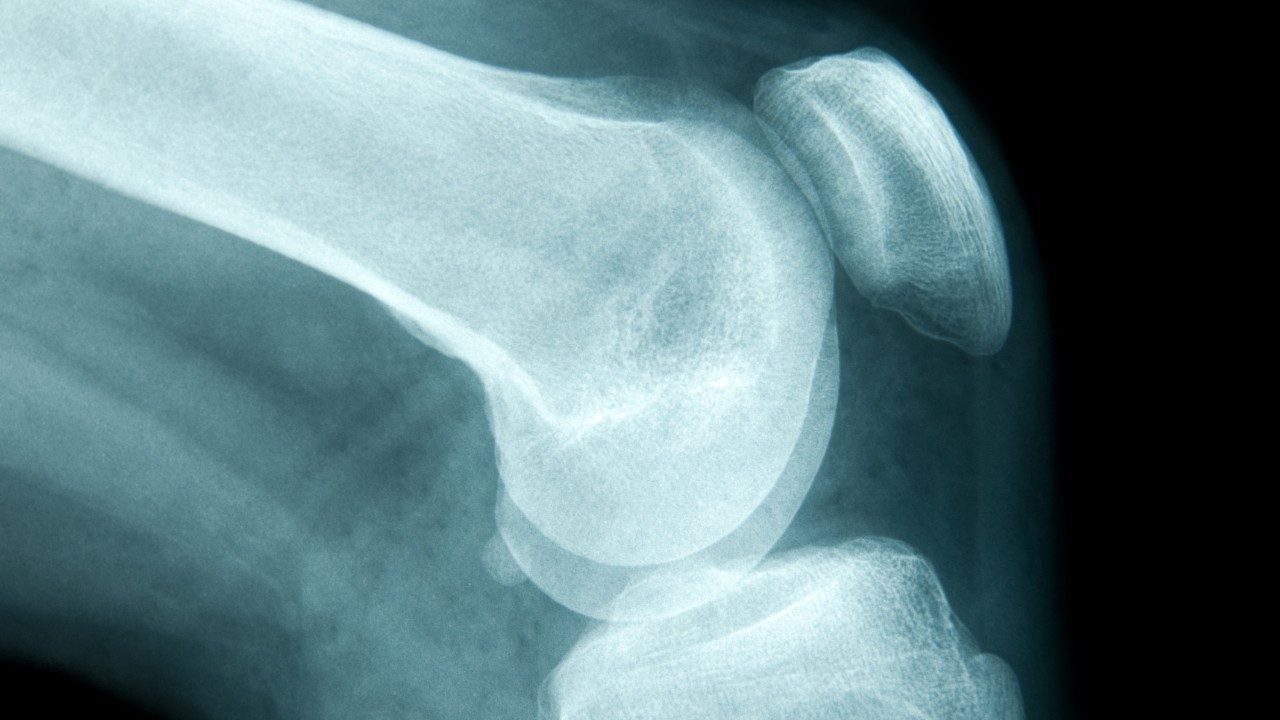

“I didn’t have any symptoms,” she says. “I got hit in the right leg while playing a softball game. When it didn’t get better after a few weeks, I had an X-ray. It turned out to be sarcoma.”

Losing bone density is common as you age, when cells that help rebuild bones aren’t replaced as quickly. Because of this, your bones may become...